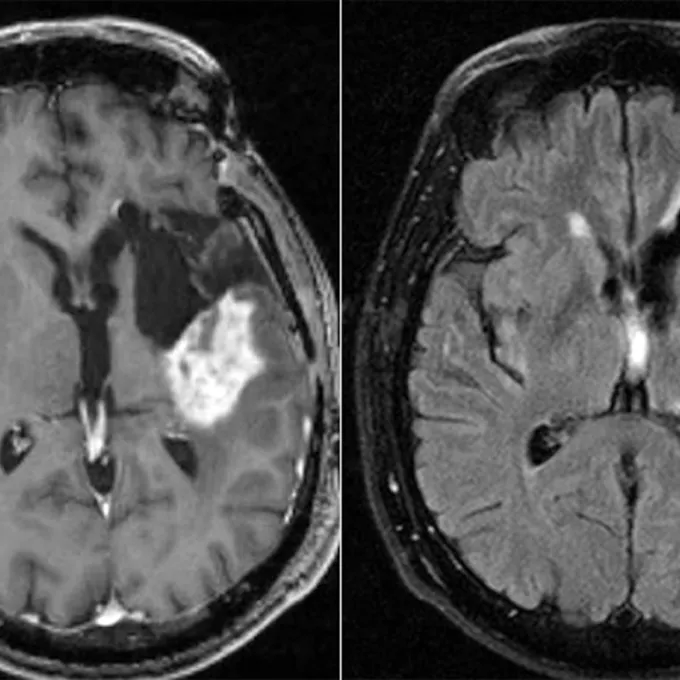

The body’s daily clock may influence cancer treatment success